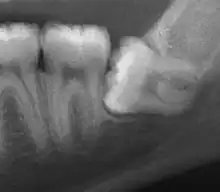

| Impacted wisdom tooth with a horizontal orientation | |

An ectopic tooth, also known as an impacted tooth, is a tooth that develops in an abnormal position and fails to erupt into its normal location in the oral cavity. [1] [2] Ectopic teeth can cause a variety of symptoms, such as pain, swelling, and infection, and they can lead to more serious complications if left untreated.

Ectopic teeth may commonly occur within the dentate region of the jaws. Other common sites for ectopic teeth include the maxillary sinus, the nasal cavity, the mandibular condyle, and the palate.[3] The cause of ectopic teeth is not always clear, but it may be related to genetic factors or developmental abnormalities.[4]

Diagnosis of ectopic teeth typically involves a comprehensive dental examination, including X-rays and other imaging tests. Treatment options for ectopic teeth depend on the location and severity of the condition, as well as the age and overall health of the patient. In some cases, observation and monitoring may be sufficient, while in other cases, surgical intervention may be necessary to remove the ectopic tooth and prevent further complications.[5]